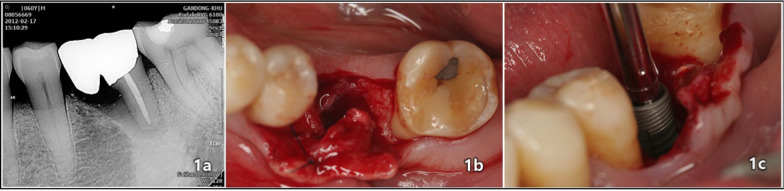

Methods: For control study, total of 23 titanium ASTM F136 grade 23 implants were placed in the edentulous molar area of the mandible. When the Implant Stability Quotient (ISQ) ≥ 70 and insertion torque value (ITV) ≥ 35-50 Ncm at the insertion site, an immediate provisional restoration was connected to the implant within a week after surgery. The definitive restorations were placed 2 months after surgery for all implants. 13 implants were immediately loaded, while 10 implants were conventionally loaded. For comparative study, Radiographs were taken from third years for and then annually for the subsequent eight years to monitor marginal bone loss.

Results: After eight year of implant installation, the average change in vertical bone loss was 0.009 mm (P < 0.001), while the average change in horizontal bone loss 8 year after implant placement was 0.026 mm (P < 0.001). The mean marginal bone loss was < 0.2 mm on average.

Conclusions: In this retrospective study, laser-treated implants exhibit a low rate of bone absorption around the implants.